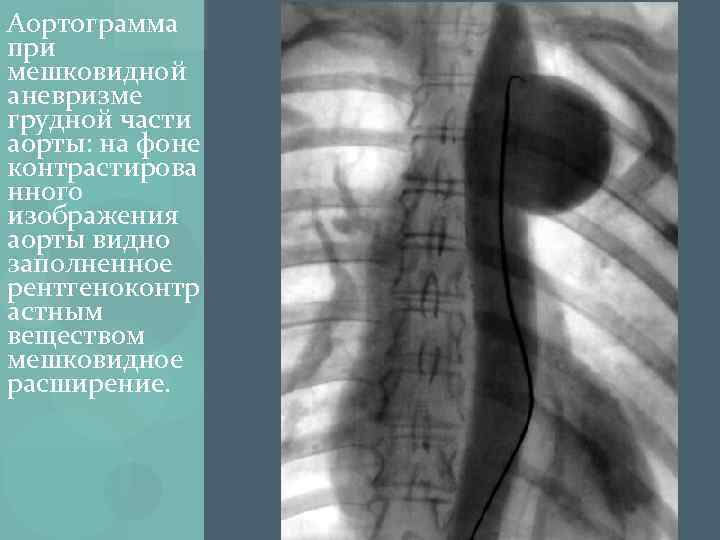

Аорта уплотнена на рентгене что это

Аорта уплотнена на рентгене что это 116 фотографий